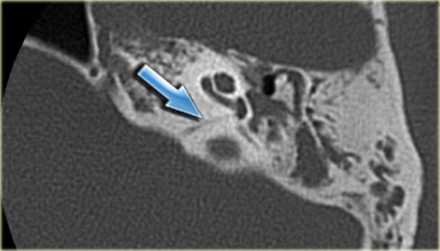

Вестибулокохлеарный нерв (VIII) состоит из 4 пучков. Опухоли происходят обычно из вестибулярной его части. Шваннома - инкапсулированная доброкачественная (градация 1) опухоль, происходящая из дифференцированных неопластических шванновских клеток оболочек периферических нервов. Невриномы ММУ составляют около 3% опухолей головного мозга. Часть шванном (двухсторонние слуховых нервов) связана с НФ 2 типа. Пик частоты между 40 и 60 годами. Растут медленно и крайне редко малигнизируются. Клинические проявления связаны с нарушением функции нерва и компрессией ствола. Шваннома может происходить из любого отрезка по ходу нерва и хорошо прослеживается при МРТ области ММУ. Невринома видна как на Т2-взвешенных, так и на Т1-взвешенных МРТ в виде округлого образования. Невриномы хорошо и равномерно усиливаются после МРТ с введением контрастного вещества. Невриномы области цистерны могут иметь компонент во внутреннем слуховом проходе, особенно, хорошо видимый при МРТ головного мозга с контрастированием. Изредка встречаются невриномы полностью расположенные внутри канальца. Они составляют наибольшую диагностическую сложность при МРТ, требуют тонких срезов и контрастирования. Менингиомы ММУ обычно типично расположены и при МРТ имеют характерную форму и типичные черты при МРТ с контрастированием. Однако редко встречаются внутриканальцевые менингиомы. При МРТ они неотличимы от неврином. Холестеатомы при МРТ имеют смешанную интенсивность сигнала, в зависимости от их содержимого. На диффузионно-взвешенных МРТ холестеатомы обычно яркие.

МРТ головного мозга. Аксиальная Т2-взвешенная МРТ. Фрагмент ММУ. Холестеатома слева.